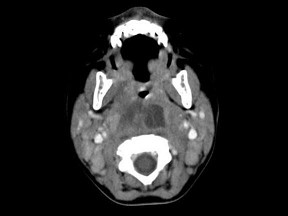

[多选题] 10个月大的婴儿,发热,曾患中耳炎,CT扫描如图所示,正确的描述或诊断是()A .咽后壁软组织肿胀B .其内密度不均C .颈椎骨质未见明显异常D .咽后壁脓肿E .咽后壁寒性脓肿

[多选题] 10个月大的婴儿,发热,曾患中耳炎,CT扫描如图所示,正确的描述或诊断是()A . 咽后壁软组织肿胀B . 其内密度不均C . 颈椎骨质未见明显异常D . 咽后壁脓肿E . 咽后壁寒性脓肿